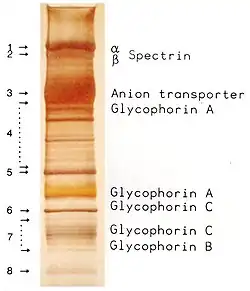

Membrane proteins

The proteins of the membrane skeleton are responsible for the deformability, flexibility and durability of the red blood cell, enabling it to squeeze through capillaries less than half the diameter of the red blood cell (7–8 μm) and recovering the discoid shape as soon as these cells stop receiving compressive forces, in a similar fashion to an object made of rubber.

There are currently more than 50 known membrane proteins, which can exist in a few hundred up to a million copies per red blood cell. Approximately 25 of these membrane proteins carry the various blood group antigens, such as the A, B and Rh antigens, among many others. These membrane proteins can perform a wide diversity of functions, such as transporting ions and molecules across the red cell membrane, adhesion and interaction with other cells such as endothelial cells, as signaling receptors, as well as other currently unknown functions. The blood types of humans are due to variations in surface glycoproteins of red blood cells. Disorders of the proteins in these membranes are associated with many disorders, such as hereditary spherocytosis, hereditary elliptocytosis, hereditary stomatocytosis, and paroxysmal nocturnal hemoglobinuria.[28][29]

The red blood cell membrane proteins organized according to their function:

Transport

- Band 3 – Anion transporter, also an important structural component of the red blood cell membrane, makes up to 25% of the cell membrane surface, each red cell contains approximately one million copies. Defines the Diego Blood Group;[32]

Structural role – The following membrane proteins establish linkages with skeletal proteins and may play an important role in regulating cohesion between the lipid bilayer and membrane skeleton, likely enabling the red cell to maintain its favorable membrane surface area by preventing the membrane from collapsing (vesiculating).

- Ankyrin-based macromolecular complex – proteins linking the bilayer to the membrane skeleton through the interaction of their cytoplasmic domains with Ankyrin.

- Band 3 – also assembles various glycolytic enzymes, the presumptive CO2 transporter, and carbonic anhydrase into a macromolecular complex termed a "metabolon", which may play a key role in regulating red cell metabolism and ion and gas transport function.

- RHAG – also involved in transport, defines associated unusual blood group phenotype Rhmod.

- Protein 4.1R-based macromolecular complex – proteins interacting with Protein 4.1R.

- Protein 4.1R – weak expression of Gerbich antigens;

- Glycophorin C and D – glycoprotein, defines Gerbich Blood Group;

- XK – defines the Kell Blood Group and the Mcleod unusual phenotype (lack of Kx antigen and greatly reduced expression of Kell antigens);

- RhD/RhCE – defines Rh Blood Group and the associated unusual blood group phenotype Rhnull;

- Duffy protein – has been proposed to be associated with chemokine clearance;[34]

- Adducin – interaction with band 3;

- Dematin- interaction with the Glut1 glucose transporter.